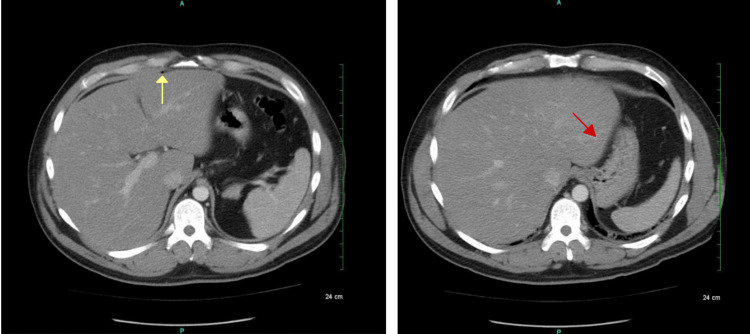

Computed tomography of the abdomen and pelvis with intravenous (IV) contrast demonstrated pockets of free air in the midline anterior abdominal wall and peritoneal cavity. (Figure 1).

There was also an air pocket tracking toward the liver margin with mesenteric induration and thickening, suggesting possible perforation. There was no free fluid, phlegmon, or fluid collections representing an abscess. The sigmoid colon revealed inflammatory changes along with the presence of scattered diverticula and colonic wall thickening, making the diagnosis of acute diverticulitis likely (Figure 2).

Additional pockets of air and an irregular hyper-dense nodular material were found in the anterior bladder along with diffuse urinary bladder wall thickening, suggestive of a CVF (Figure 3).